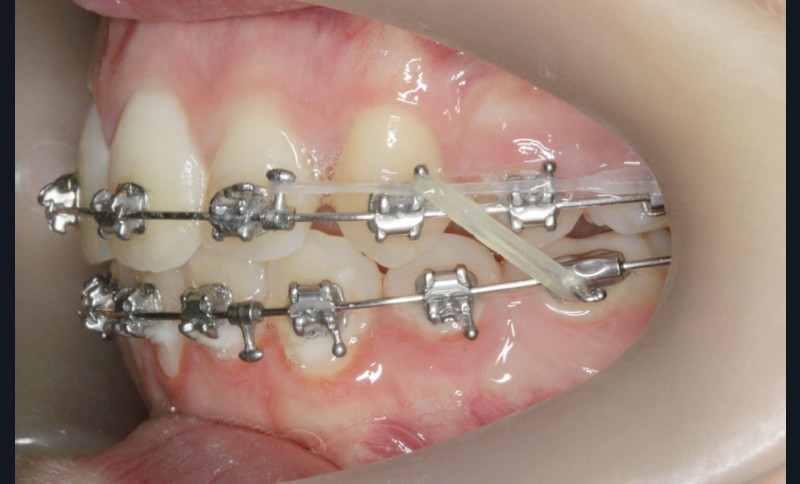

Le site des extractions s’est porté sur les secondes prémolaires. La justification de ces extractions passent par la résolution de l’encombrement sans effondrer le prémaxillaire.

La résolution de la classe II squelettique n’est aucunement recherchée au travers des extractions mais par une mécanique interarcade.